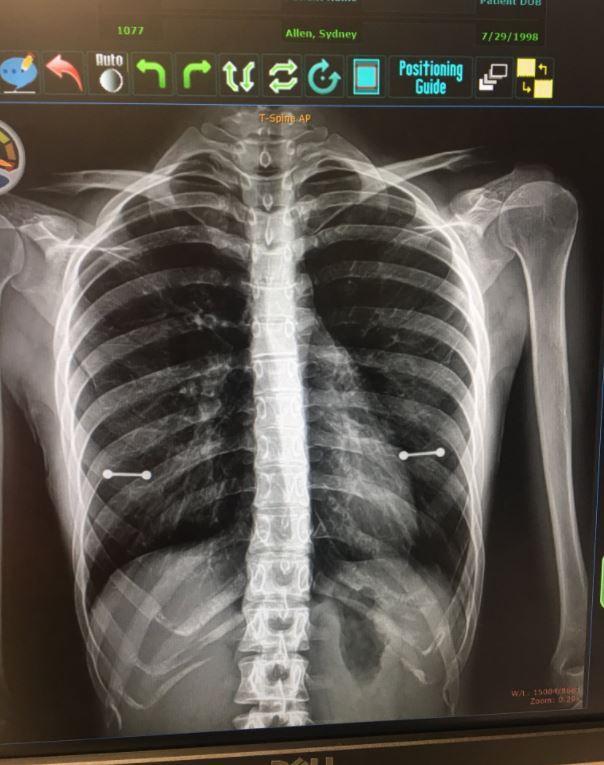

▼原來西妮最近被發現罹患了脊髓空洞症(Syringomyelia),必須持續追蹤檢查以便進行治療矯正,不過這次醫生對她進行X光檢查時,因為忘了提醒必須將所有穿孔飾品拿掉,讓X光照清楚的拍出她的乳房處有2條「金屬槓」,雖然醫生和護理師看了之後當場大笑,不過陪同在旁的母親卻是一秒變臉,生氣的向女兒表示「我們等下來討論一下這個問題」。

▼原來這個乳環是西妮在今年6月時和閨蜜一起去穿的「生日禮物」,不過媽媽並不知情。之後西妮也在自己的推特上寫道「今天我媽媽發現我在乳頭打洞了」,同時附上X光的照片,很快就吸引了超過20萬名網友按讃!